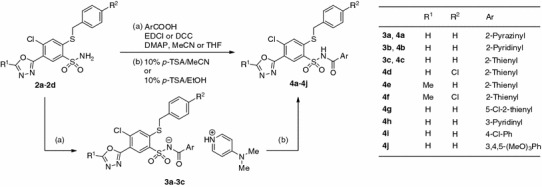

The desired N-acylsulfonamides 4a–4j (Scheme 2) were prepared by carbodiimide-mediated coupling of aromatic carboxylic acids with sulfonamides [32–34] promoted by 4-(N,N-dimethylamino)pyridine (DMAP) in the appropriate solvent. In some cases crystalline 4-(N,N-dimethylamino)pyridinium N-heteroaroylsulfonamidates (3a–3c) were isolated and characterized, which by treatment with 10% (w/v) ethanolic p-toluenesulfonic acid (p-TSA) solution were converted to the desired N-acylsulfonamides 4a–4c.

Scheme 2.

Over a series of N-(thien-2-ylcarbonyl)benzenesulfonamide derivatives (4c–4g), substitution on the heterocyclic (4e, 4f: R1 = Me) or benzylthio (4d, 4f: R2 = Cl) moiety decreases activity significantly. It seems interesting that closely related six-membered N-heteroaroyl derivatives (4a, 4b, and 4h) showed no activity, which renders 4c as a lead for further optimization.